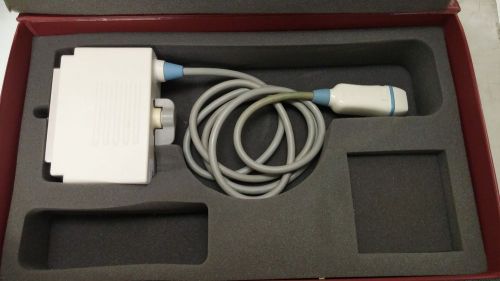

PHILIPS/ ATL C8-5 14R Micro Convex Curved Array Ultrasound Transducer Pediatric

PSK-25AT Ultrasound probe with warranty

Agilent Technologies 21369A / T6210 Omni-Plane II Trans-Esophageal Probe (12449)

Philips S3 Ultrasound Transducer Probe 21311A (KK)

GE IC5-9-D ULTRASOUND PROBE (GG)

GE RNA5-9-D Convex 4D Ultrasound Transducer Probe (AA)